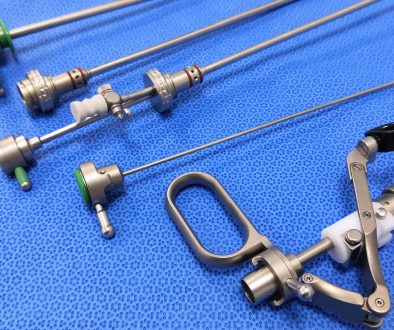

الحقن المجهري هو إجراء طبي يتم فيه حقن حيوان منوي مباشرة في بويضة ناضجة. تُستخدم هذه التقنية لعلاج العديد من حالات العقم عند الذكور مثل ضعف الحيوانات المنوية أو تشوهاتها. يُعد الحقن المجهري جزءًا من عملية أكبر تُعرف بالتلقيح الصناعي.

التلقيح الصناعي هو عملية تُخصب فيها البويضة بالحيوان المنوي خارج الجسم في بيئة مخبرية، ومن ثم تُزرع البويضة المخصبة داخل الرحم. يُستخدم التلقيح الصناعي لعلاج العديد من الأسباب التي تؤدي إلى صعوبة الحمل مثل انسداد قناتي فالوب، أو مشاكل التبويض، أو العقم غير المفسر.